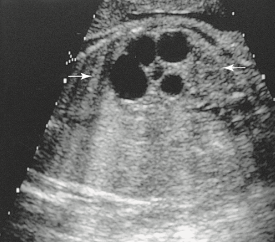

During a late second-trimester screening examination, what does this image of the fetal abdomen most likely show:

infantile polycystic disease

Which of the following conditions will likely occur because of this abnormality?

oligohydramnios